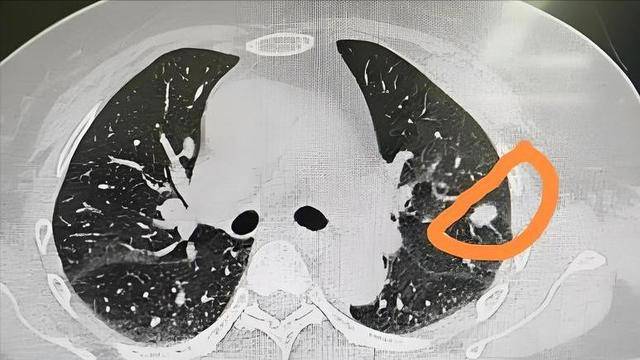

如果三个月后复查发现结节明显缩小甚至没了,那就不用太担心。但如果三个月后结节大小没变,或者还增大了,那性质可能就不一样了。

这个阶段的观察,其实就是在做“筛选”。医生不会贸然判断结节的恶性与否,而是用时间去观察它的“性格”。有研究显示,约有30%的肺部小结节属于良性炎症性病灶,在三个月内就能稳定或消退。

这个数据说明了不少早期结节只是虚惊一场,但如果因为粗心大意没复查,那这些数据就和你没关系了。而一旦真的出现了增长趋势,三个月的时间也刚好能卡在早期干预的窗口期。错过这个时候,等发现结节已经长到超过8毫米,甚至形成实性成分,再来处理就没那么简单了。

-   判断生长趋势:如果三个月后复查CT发现结节明显缩小或消失,则良性可能性极大。若结节大小无变化甚至增大,或密度、形态发生改变,则需进一步警惕其恶性的可能性。

这个阶段的复查能帮助医生初步判断结节的“活性”,避免将短期炎症误判为恶性肿瘤,也能及时发现快速增长的可疑病灶。